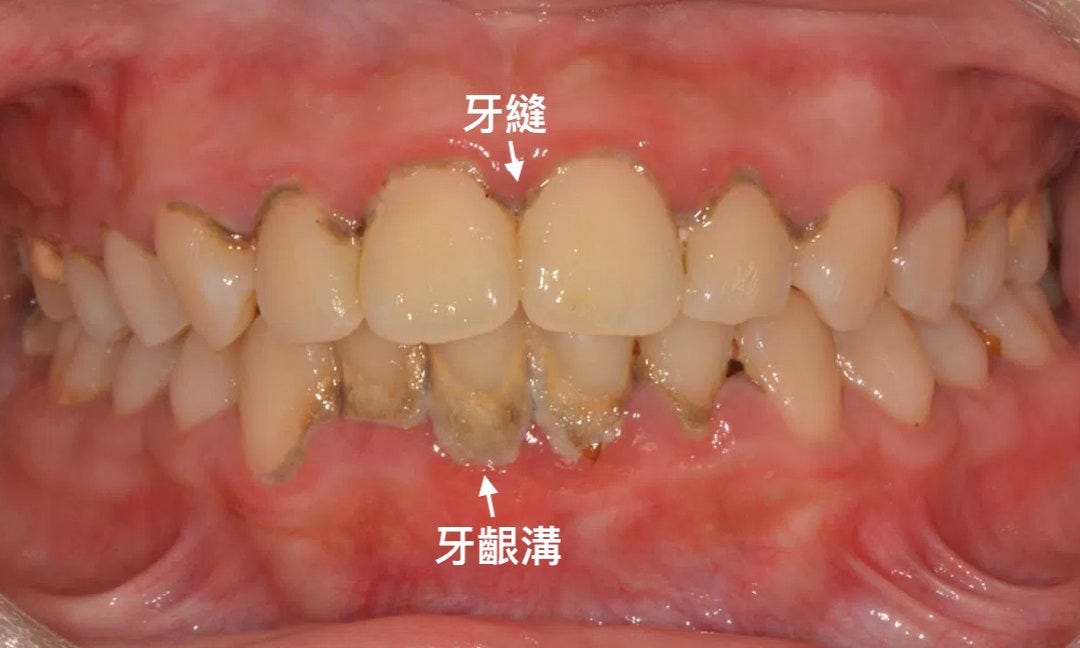

口腔細菌和食物最容易躲在牙齦溝(牙齒和牙齦交界)和牙縫(牙齒和牙齒交界)

萬惡的海綿牙棒沒有能力進入凹陷處清潔

但倒是有把食物、細菌塞進牙縫裡的能力😂😂😂